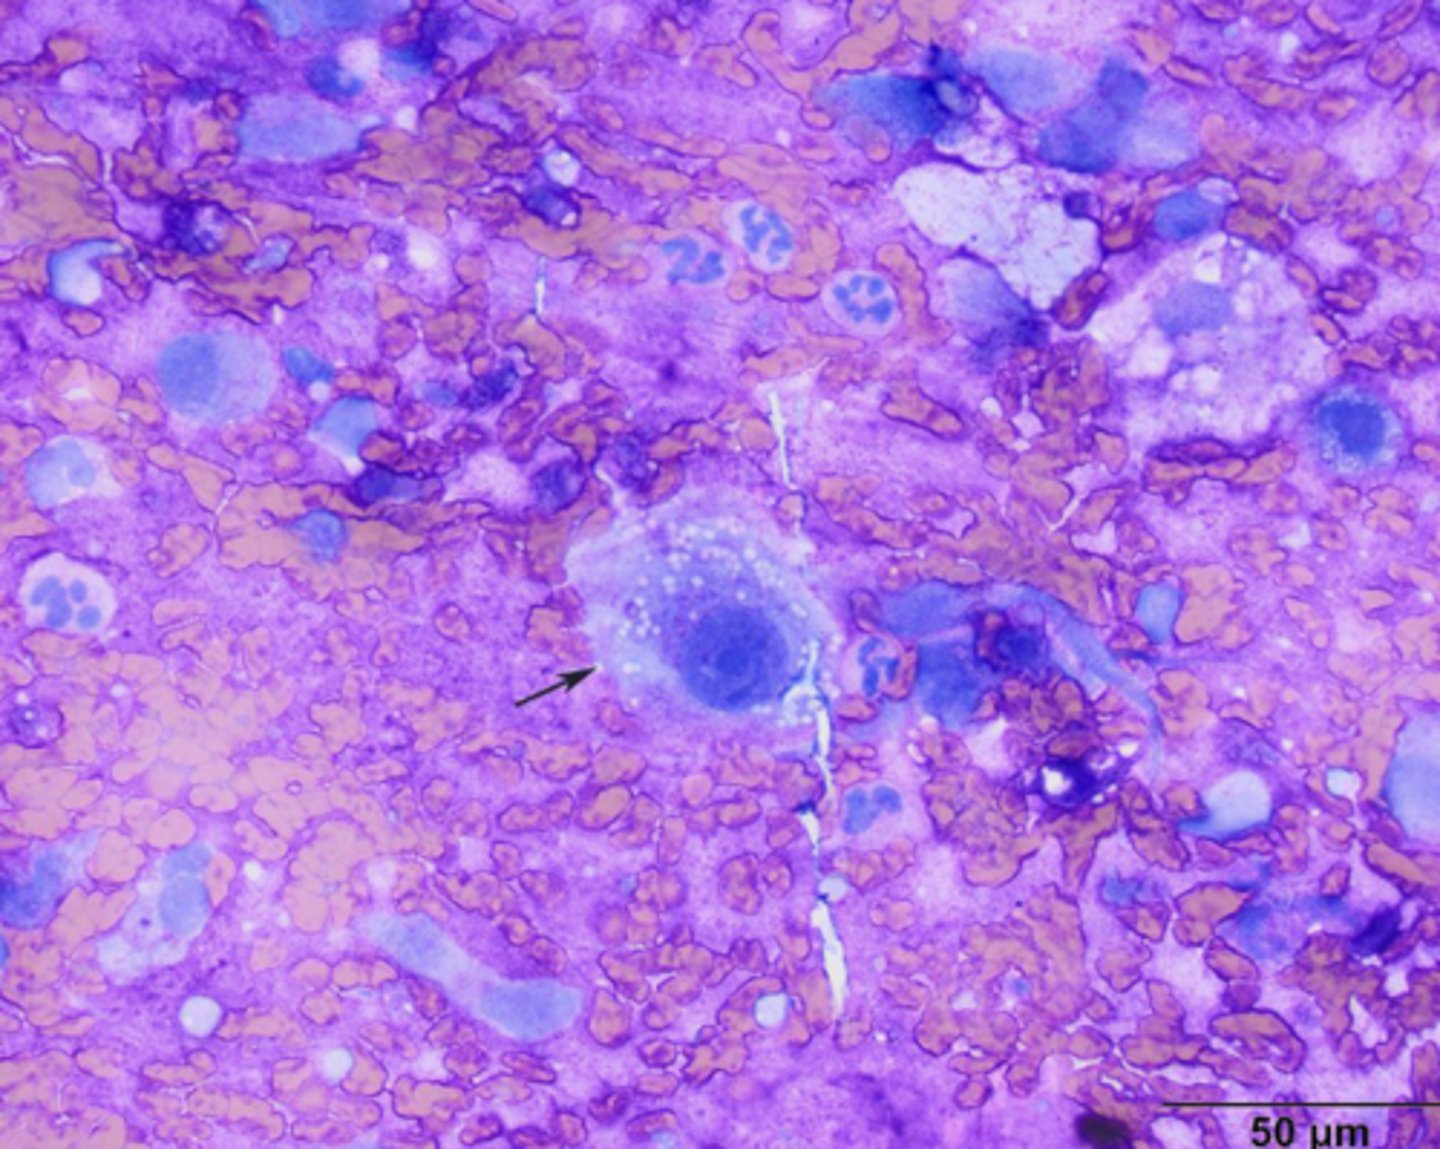

Transmissible Venereal Tumor (TVT)

-cells have a medium to large round nucleus, possibly eccentric

-clumped chromatin, common to see mitotic figures

-multinucleation

-cytoplasm light blue/gray with discrete vacuoles